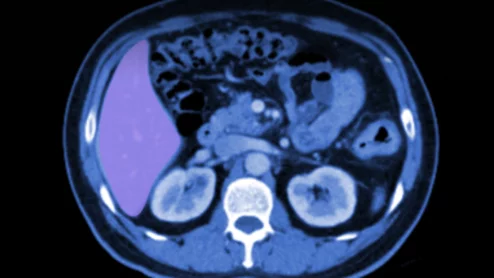

CTC colonography colon cancer colonoscopy

CT for CRC screening is at an “inflection point” following the Centers for Medicare & Medicaid Services’ recent decision to cover the exam, experts say.